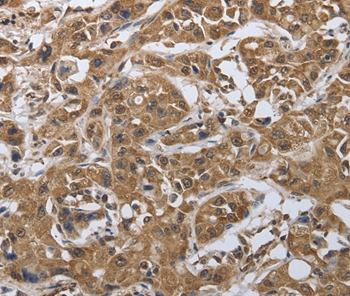

Immunohistochemical analysis of paraffin-embedded Human cervical cancer tissue using #37037 at dilution 1/20.

Immunohistochemical analysis of paraffin-embedded Human lung cancer tissue using #37037 at dilution 1/20.